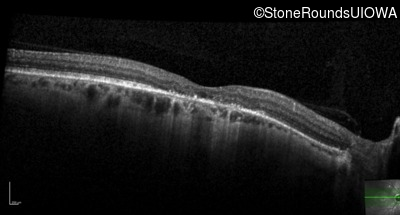

This 52 year old man had normal vision until his mid 30's when he began to have trouble distinguishing colors. the issuing 10 years he had a gradual loss of visual acuity accompanied by increasing photophobia.

| Age at visit: 61 years |

| Age at visit: 64 years |